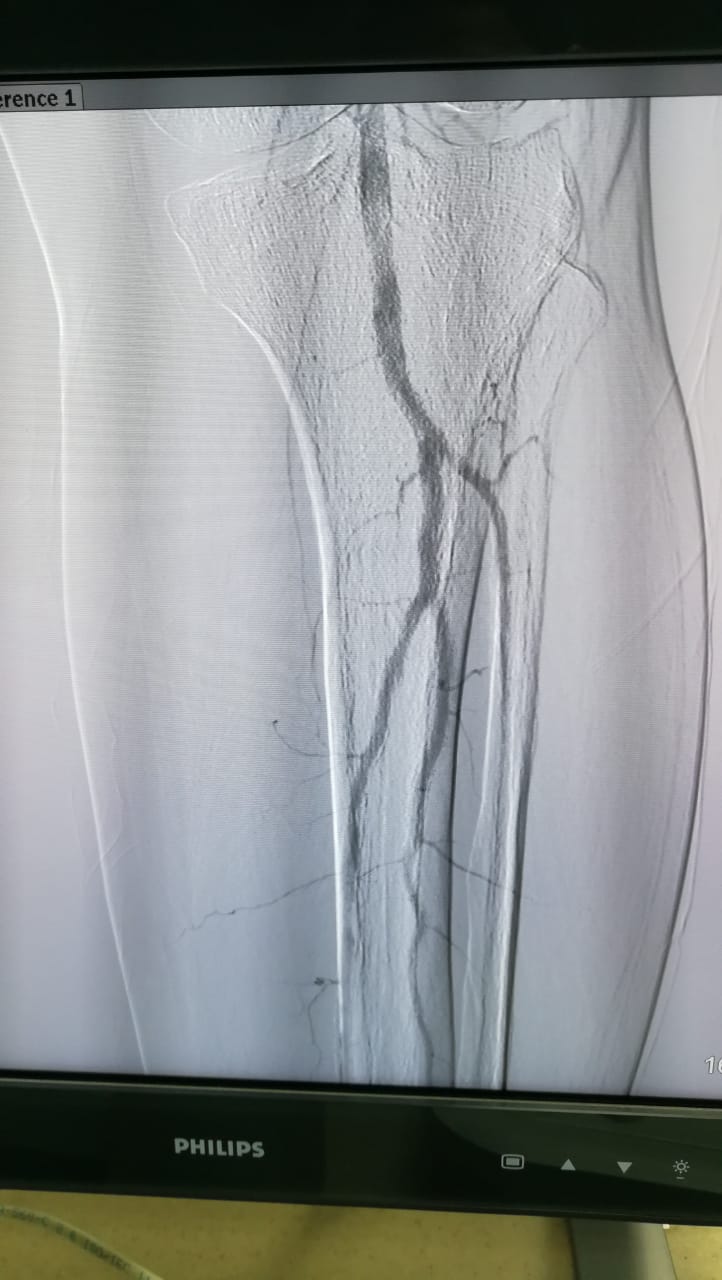

اجراء ٣ حالات توسيع للشرايين الطرفية لمرضى القصور الدموى الحرج بمستشفى المنصورة الدولي

صرح الدكتور سعد مكي وكيل وزارة الصحة بالدقهلية عن إجراء عدد ثلاث حالات تعانى من قصور دموى حرج بالشرايين الطرفية تحت الركبة وذلك داخل وحدة القسطرة الطرفية بمستشفى المنصورة العام الجديد (الدولى) ضمن خطة المستشفى للقضاء على قوائم الانتظار وتقديم خدمة طبية عاجلة لمرضى التأمين الصحى ونفقة الدولة.

تكون الفريق الطبي من الدكاترة هانى حسنى رئيس قسم جراحة الأوعية الدموية واحمد فكرى اخصائي جراحه الأوعية الدموية وعلى البرادعى اخصائي جراحه الأوعية الدموية واحمد عطية؛ طبيب مقيم جراحة الأوعية الدموية ورضا عويس طبيب مقيم زمالة جراحة الأوعية الدموية و عبدالرزاق غبدالرازق طبيب مقيم زمالة جراحة الأوعية الدموية وبمساعدة فريق القسطرة الطرفية بحضور أطباء قسم جراحة الأوعية الدموية.